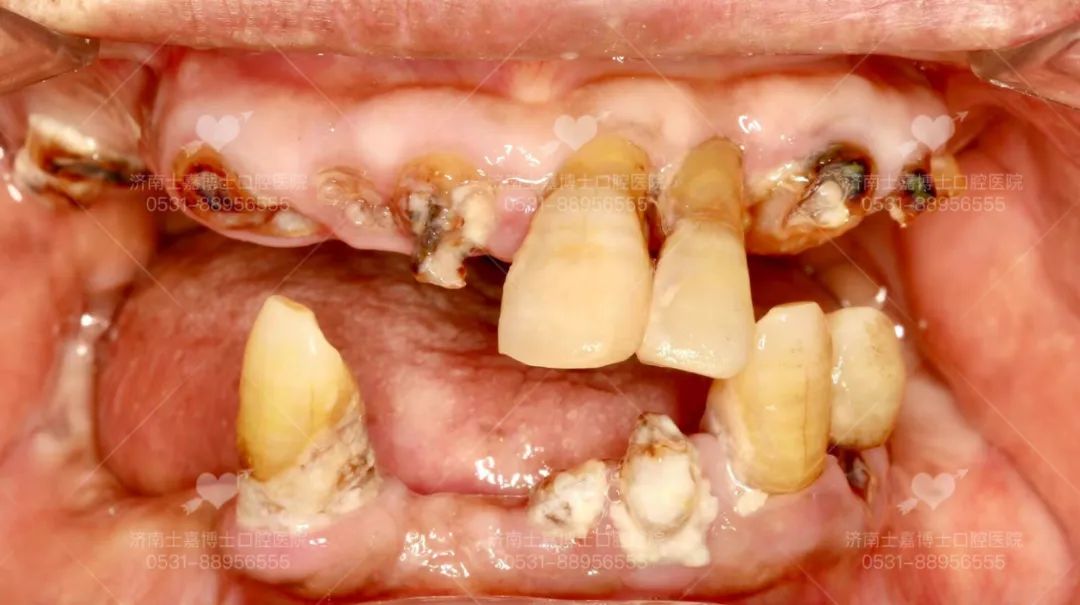

医生技术好 · 种牙不受罪 · 牙齿用到老 种植牙的成功与长久使用,与医生的医疗技术和水平及医院的设备有着直接的关系。那么由谁种,是种植牙成功的关键! 下面将从几个方面来看,如何选择一个好的种植医生。 一、看学历/资质 学历背景很重要,尽量选择口腔医学院校毕业的医学生,这些在专业口腔医学院校接受的培训和掌握的技术更规范和先进,水平较高的种植医生一般都是硕士、博士级别。 二、看进修背景 种植科医生会不断进修,一般选择口腔专科医院或是大型综合三甲医院口腔科或是国外的牙科学院进行进修学习 三、看种植技术,尤其是复杂种植完成质量 医生技术好,种植后就极少出现种植体与骨之间愈合不好而导致的牙松动、脱落等,越能把握种植牙长期效果,尤其是针对复杂牙种植后的完成质量,更是“一牙见分晓” 种植过程中,技术好的医生对种植体植入到牙槽骨的把握力度更好,对于基台穿龈的准确度就越高,为保证种植牙长久的使用打下良好基础 尤其是中老年人普遍面临着半口/全口缺牙、长期缺牙、牙槽骨萎缩吸收等难题,传统种植技术对老人身体损伤较大,导致无法实现种牙。而娴熟掌握先进技术的种植医生,能够做到少植骨或不植骨,更能保证种植后的效果和质量 四、看种植案例数量 种植牙是一项精细的医学手工技术,一般来说,临床经验越丰富,医生技术就会越好,种了100颗牙与种了10000颗牙的医生,在技术经验是有很大差别的,针对牙齿种植,所种植的数量越多,就能更好的帮患者患者减少种植过程中的手术痛苦、保证种植牙的长久使用 所以,选择医生一般都会选择种植经验丰富,这在很大程度上决定了种植牙后期的使用效果以及使用寿命 士嘉博士口腔医院舒适化种植团队 从种植体设计、生产,到医生把种植体植入牙槽骨,再到完成种植后患者的个人生活习惯,每一个环节、每一个细节都会影响种植体表面骨改建的动态平衡,继而影响种植成功还是失败。 因此,选择一个有经验有技术的种植医生尤为重要。 张士杰,山东大学口腔医学院博士研究生导师、教授、博士后,山东大学齐鲁医院口腔正畸科主任、主任医师。中华医学会口腔正畸专业委员会委员,中华医学会整形美容牙颌颜面美容分会常委,世界正畸联盟WFO会员。曾赴日本东京医科齿科大学、美国康州大学牙医学院、美国哈佛大学种植研修中心访问交流。发表学术论文四十余篇,其中被SCI收录十五篇,获山东省科技进步三等奖一项。承担国家自然科学基金、山东省自然科学基金、山东省科技攻关、山东大学自主创新、山东省重大专项等多项科研项目。口腔临床技能全面,以先进技术为基础、结合国外口腔诊疗服务理念,通过口腔正畸、种植修复、牙周治疗、牙齿美容等全面为患者提供适合的治疗方案,注重人文关怀。 擅长:成人及青少年各类牙齿畸形的矫正治疗,隐形矫正(山东省首批美国隐适美隐形矫正认证专家),在诊疗牙齿前突、开唇露齿、地包天、唇腭裂等正畸正颌联合手术治疗方面尤其突出,尤其擅长复杂牙列缺失的种植修复和咬合重建治疗。 高万郝,主治医师,山东大学口腔医学硕士,北京大学口腔医学院进修 擅长:各类牙齿种植、智齿拔除等口腔手术,熟练掌握多套国际先进的种植系统有多年口腔种植临床经验,尤其擅长复杂病例的咬合重建 病例分享一:77岁老人全口种植 父亲节当天,77岁的老人来士嘉博士口腔全口种植,老人得过脑梗、有心衰,本不想做牙齿上的治疗,在儿子坚持下做了种植,当天做到即刻拔牙即刻修复即刻全口种植,拔牙后吃上肉包子,由衷的感叹:香! 病例分享二:80岁奶奶上半口种植初体验 奶奶说“效果很好,牙齿很漂亮,一点都不痛!” 五、看选择的种植机构 口腔种植学,不仅是独立的学科,且涉及口腔颌面外科学、修复学、牙周病学、材料学、生物力学、影像学等口腔各学科领域。 先进的种植仪器 士嘉博士口腔医院坚持设备与国际同步,倡导舒适化的诊疗理念 我们引进了德国卡瓦3D数字化影像设备、德国3D瓷睿刻数字化牙椅旁修复系统、德国3D打印数字化种植导板系统、瑞士美国德国韩国等世界品牌种植系统等 能够提供当天就诊、当天戴牙,大大缩短了患者的等待时间。个性化服务更好,义齿生产质量更精密,还能快速解决临床戴牙所遇到的问题,更舒适、效率更高,客户满意度大大提高